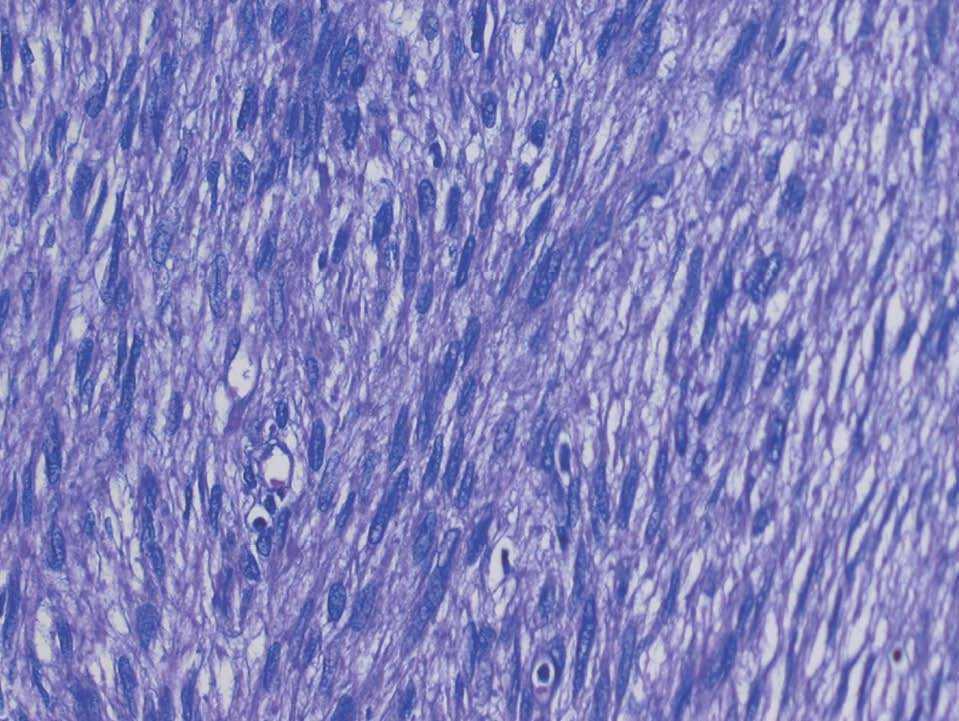

Histológicamente, la tumoración estaba constituida por células de morfología fusiforme, citoplasma eosinófilo, con un patrón fibrilar de límites imprecisos, y núcleos elongados con bordes romos y cromatina fina (fig. 2). No había necrosis tumoral ni patrón infiltrativo en los márgenes tumorales. Tampoco se observaban áreas mixoides, y la celularidad mostraba una atipia nuclear de forma focal en algunas áreas, aunque sin adquirir un grado pleomórfico (fig. 3). Según las áreas, había abundantes figuras mitóticas que oscilaban, en los distintos recuentos realizados, entre 5 y 7 mitosis por cada 10 campos de gran aumento. El estudio inmunohistoquímico realizado mostró una intensa positividad para vimentina, actina músculo liso (fig. 4) y desmina, así como para los receptores de estrógenos y la progesterona; las queratinas y la proteína S-100 fueron negativas.

Figura 2. Patrón fusocelular con núcleos de bordes romos y atipia (HE, ×20).